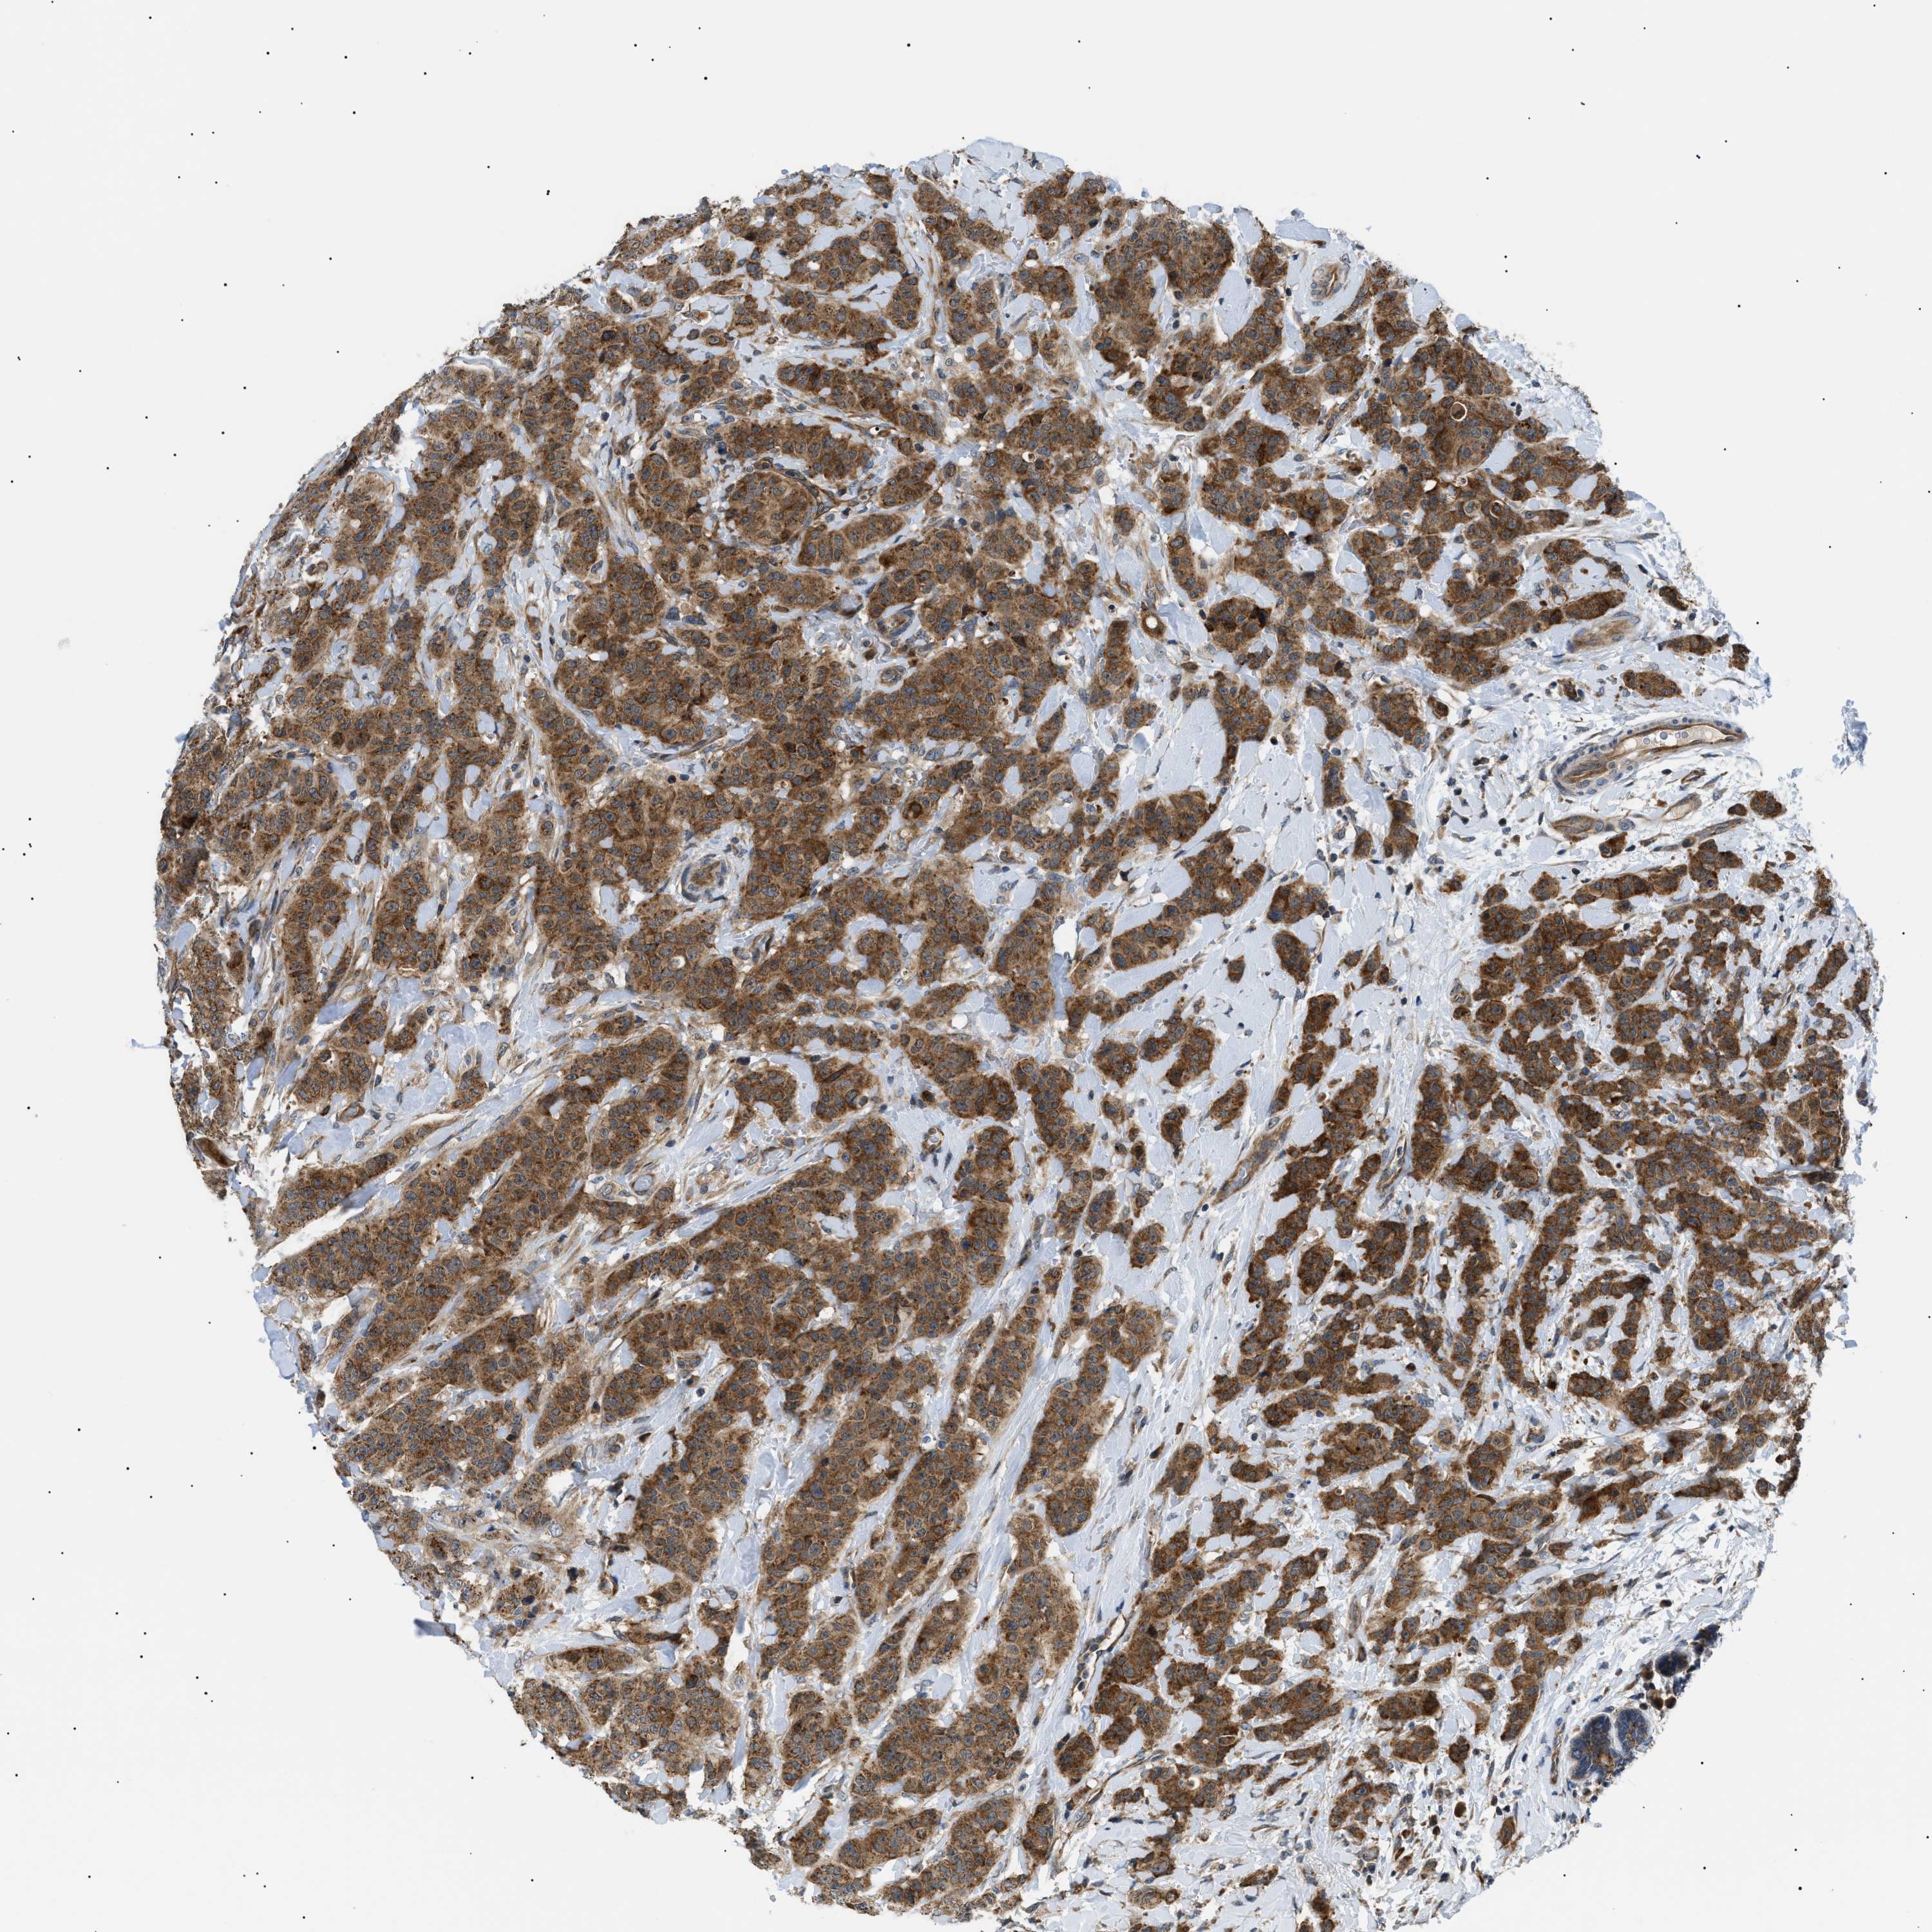

CANCER BREAST CANCER Show tissue menu

BRCA TCGA BRCA VALIDATION PROTEIN EXPRESSION